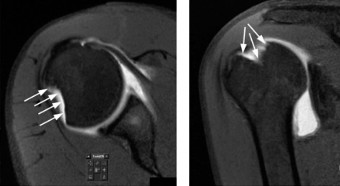

Identify the muscles that compose the force couples in the transverse and coronal planes? CASE 3 A 35-year-old male has had left shoulder pain for 4 months, ever since a low-speed motor vehicle accident (MVA). Physical examination demonstrates preserved range of motion but pain and some weakness with Jobe’s testing. His imaging is shown in Figure 2–8.

Figure 2–8_Reproduced with permission from Stadnick ME. _Partial Rotator Cuff Tears. MRI Web Clinic. 2007 (Apr).

What is the most likely diagnosis?

The correct answer is (A). These are best diagnosed on an MRI as seen in the imaging provided; addition of intra-articular contrast can further improve this study. Answer B, full-thickness rotator cuff tear, is incorrect as the bursal side of the tendon can be seen to be in continuity. Answer C, a SLAP lesion, will be visualized as a labral tear on a coronal MRI and will be found at the biceps root. Answer D, an ALPSA lesion, will be most clearly seen on an axial MRI. It is a variant of a Bankart lesion where the labrum is displaced medially and inferiorly rolling down the glenoid neck underneath the periosteum.

MRI remains the most popular imaging modality for diagnosing rotator cuff tears. Normal rotator cuff tendon appears dark on both T1 and T2 sequences. Tears may be noted as being full-thickness, articular-sided, bursal-sided, or intrasubstance. They are visualized as a disruption in the regular contour of the tendon and increased signal intensity on T2 sequences. Occasionally, an MR arthrogram may provide additional information regarding a cuff tear, although this is not routinely ordered.